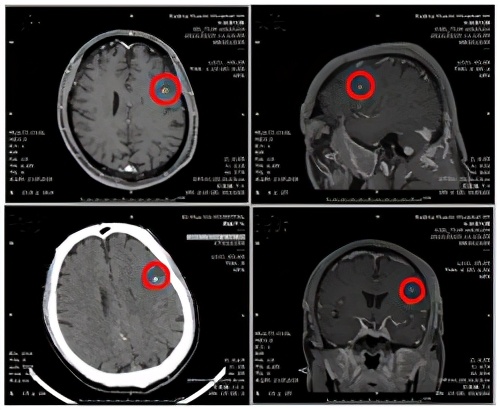

在随后的头颅核磁检查结果显示,患者左侧额叶有一大片异常信号,隐约可以看到中心有团块样东西,进一步完善头颅增强核磁检查,看到水肿带中间有一个环形强化结节,再结合头颅CT同一位置的高密度影,这些蛛丝马迹不禁让医生猜测:患者囊虫病治愈后已过去15年,真凶还可能是此病吗?或是脑肿瘤?右侧中脑亦见点状强化灶,是颅内多发转移瘤?

继续完善检查,患者经腰椎穿刺脑脊液压力升高,脑脊液常规、生化、细胞学均正常。外送血及脑脊液免疫系列、副肿瘤系列及囊虫、曼氏猎头蚴、肺吸虫抗体检查均阴性,被奉为感染性疾病“金标准”的二代测序检查,也未检出囊虫核酸。

与患者及家属充分沟通后给予驱虫治疗,10天后患者头痛症状逐渐好转,未再发作癫痫。复查核磁检查,病灶较前明显缩小,更验证了神经内科医师此前做出的诊断。